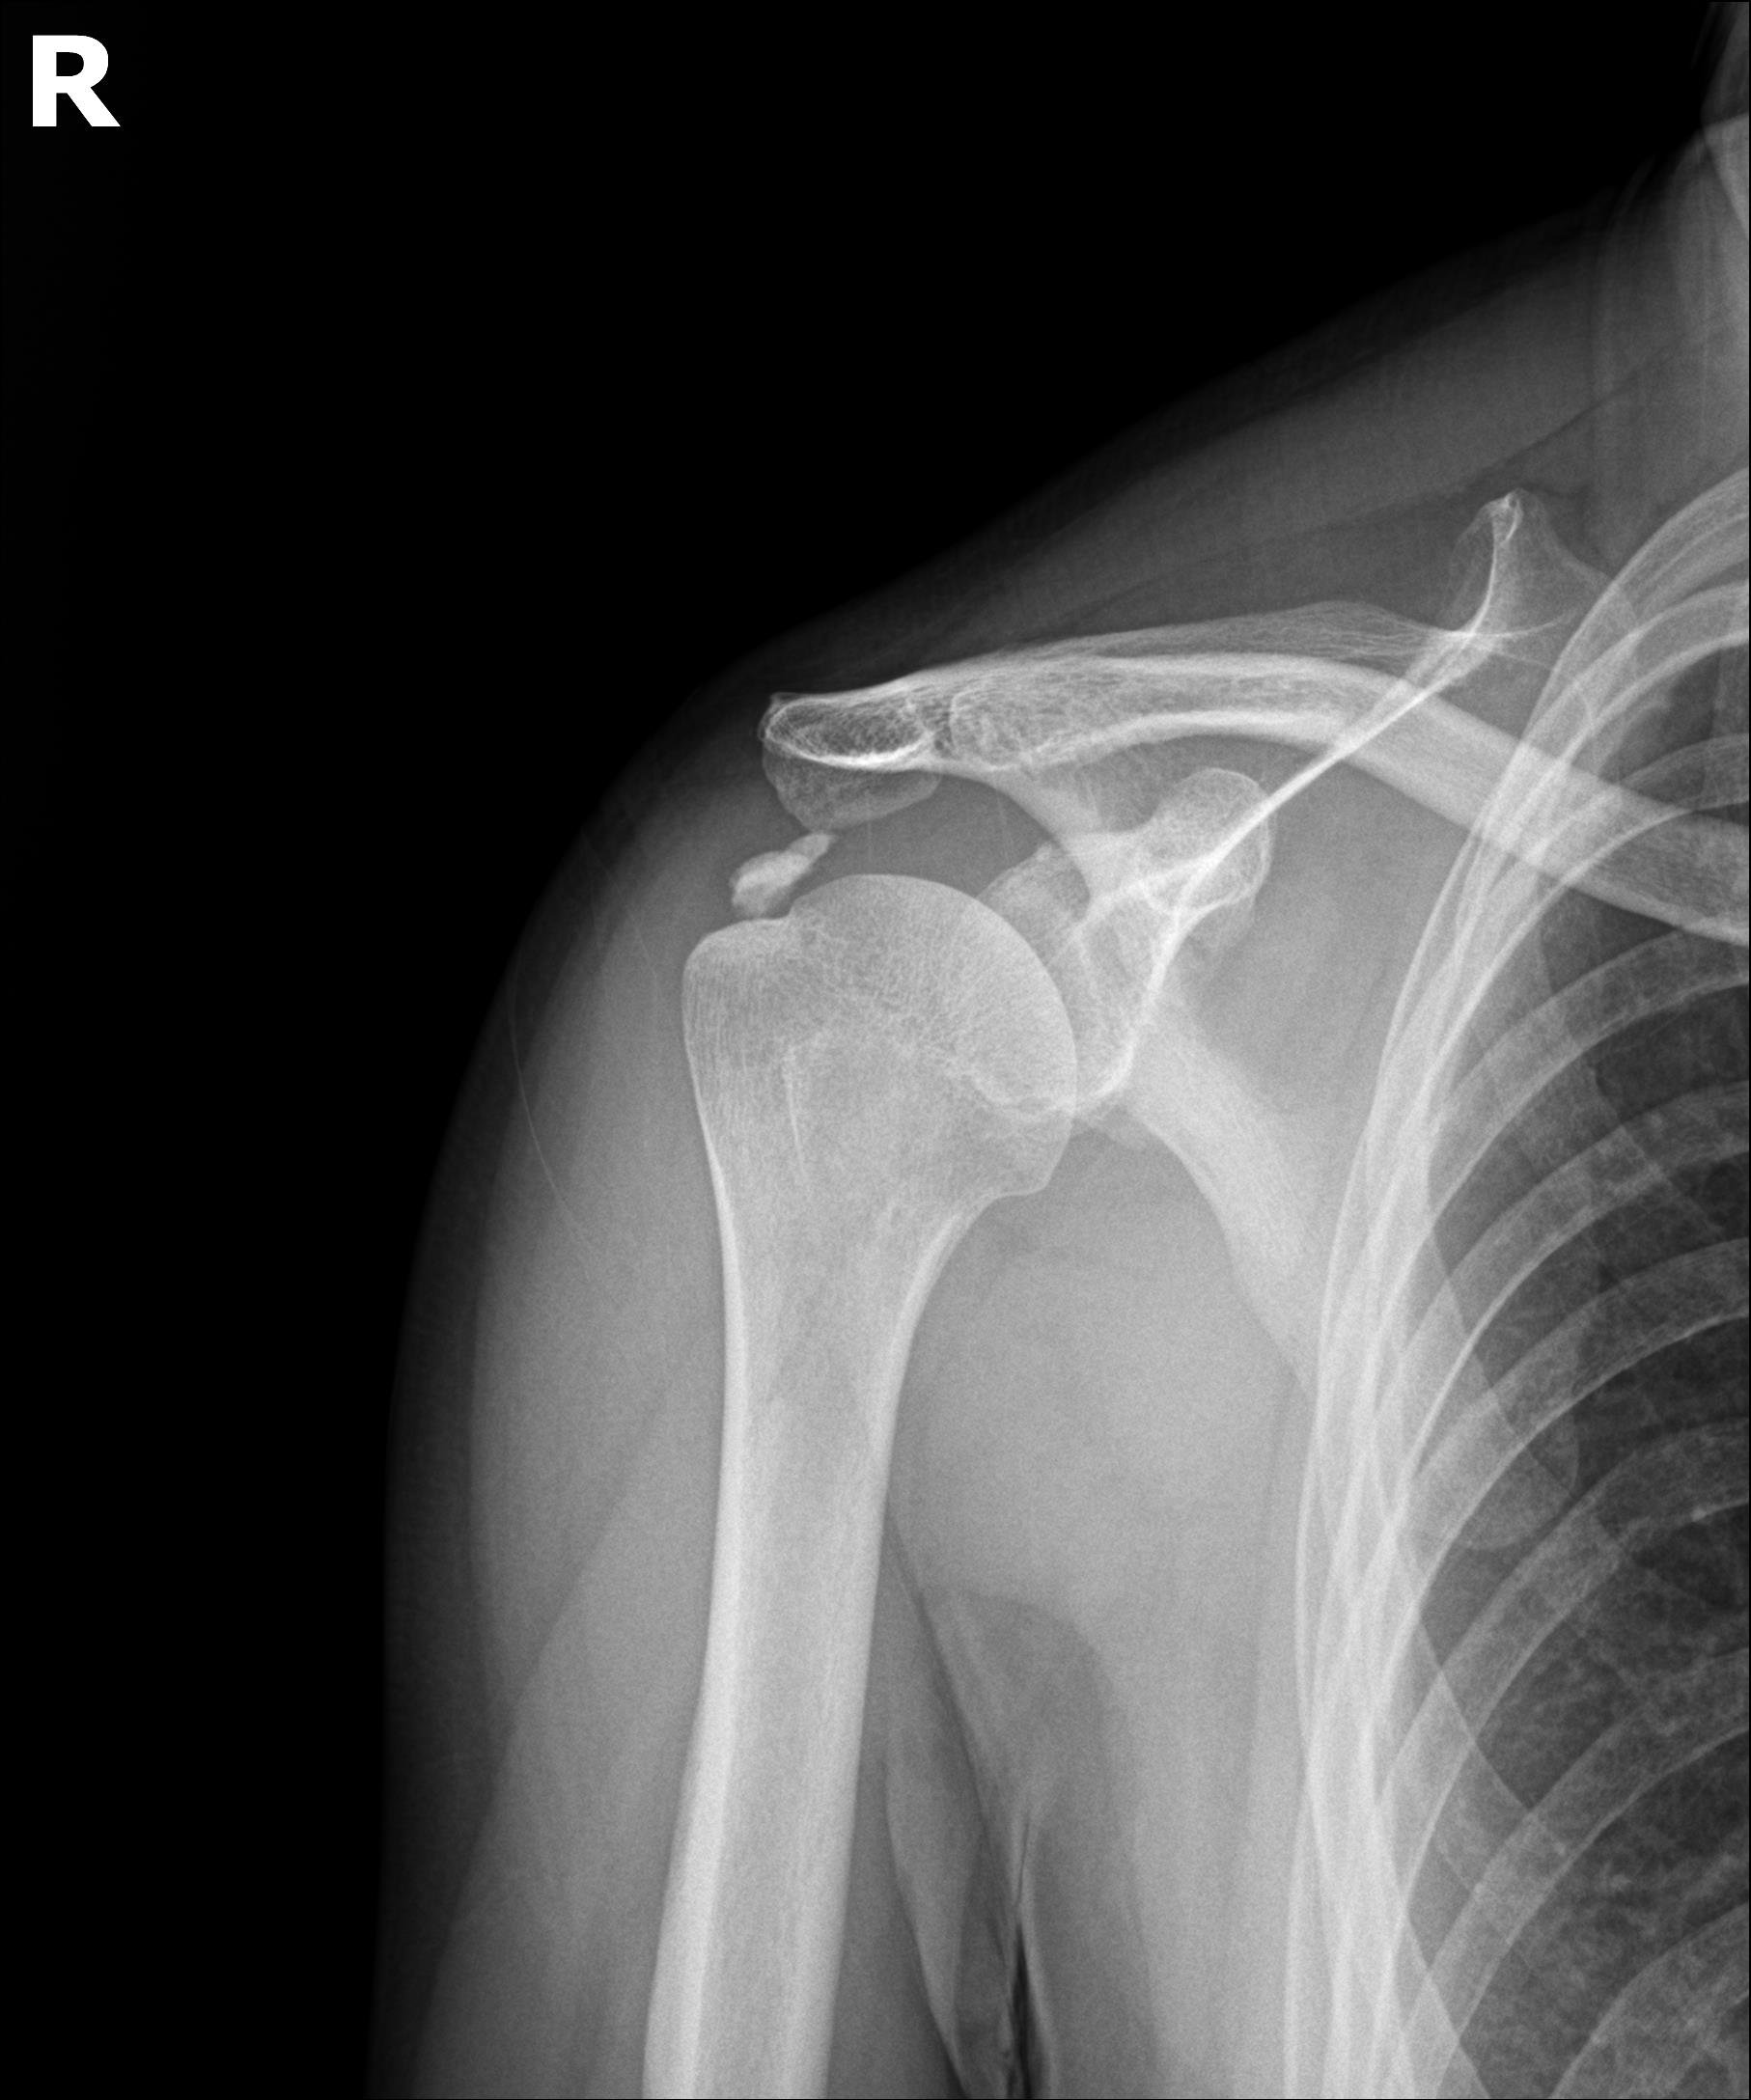

타 병원 시술 실패 원인 분석

환자분이 가져오신 이전 병원의 영상 자료를 검토했습니다.

문제점:

1세대 방법 사용: 주사바늘로 찌르고 씻어내는 방식

단단한 석회: 형성기~휴지기 석회였음

인대 손상: 반복 시술로 인대 주변 염증 발생

석회 잔존: 3회 시술 후에도 석회 대부분 남아있음

플래티넘에서의 치료

진단:

X-ray: 약 1.3cm 석회 (휴지기)

시술 직후 X-ray에서 석회 완전 제거 확인